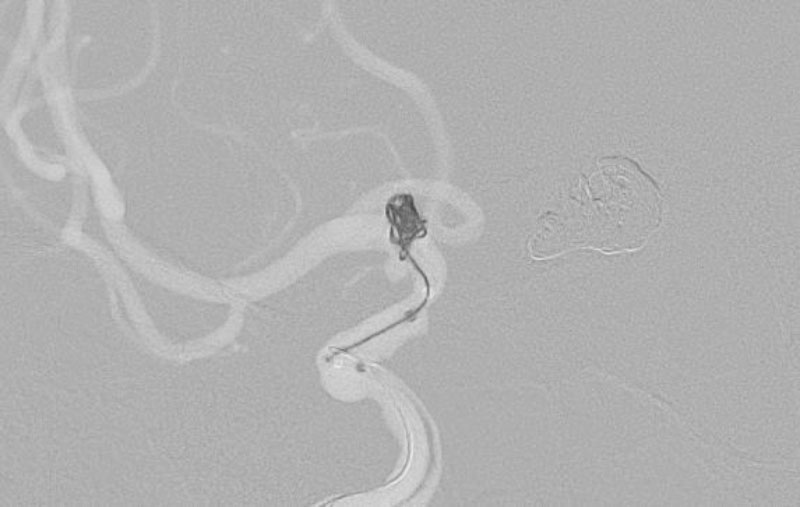

'25年10月

くも膜下出血

前交通動脈瘤破裂

40代

大阪府の病院

No.1589 手術前

No.1589 手術中

No.1589 手術後